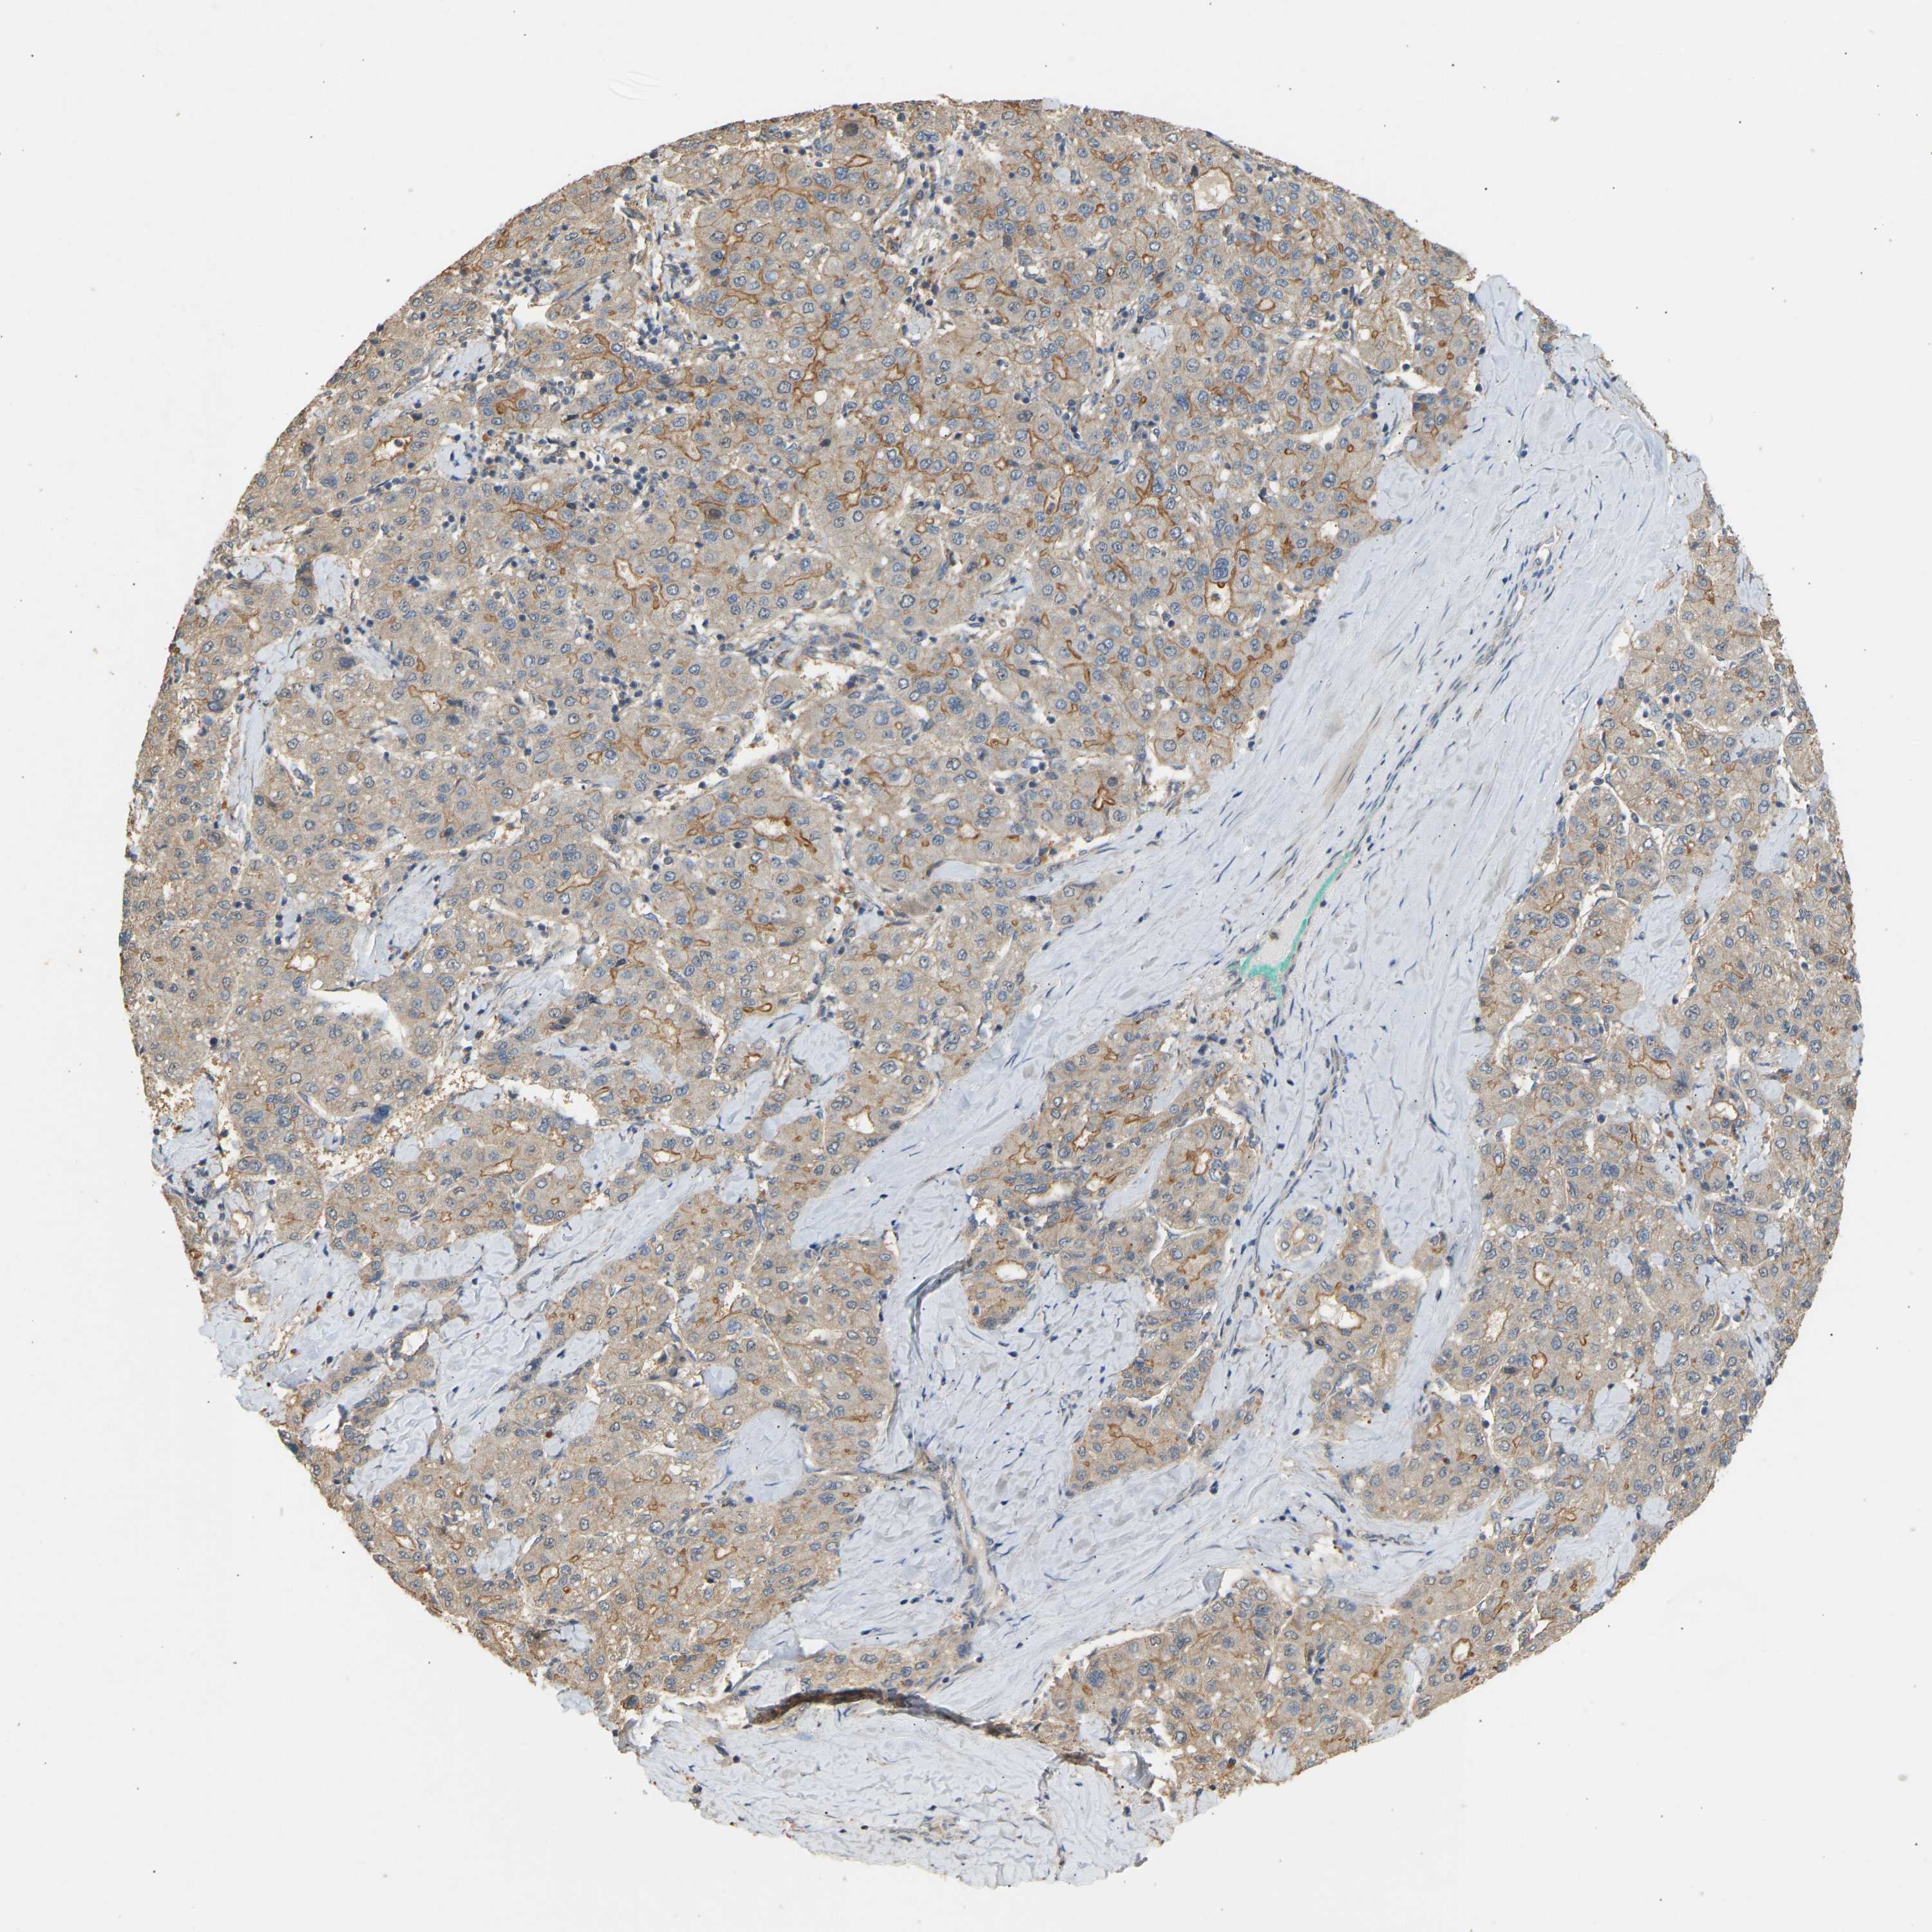

LIVER CANCER - Protein expressioni

A mouse-over function shows sample information and annotation data. Click on an image to view it in a full screen mode. Samples can be filtered based on level of antibody staining by selecting one or several of the following categories: high, medium, low and not detected. The assay and annotation is described here.

Note that samples used for immunohistochemistry by the Human Protein Atlas do not correspond to samples in the TCGA dataset.

Antibody stainingi

Antibody staining in the annotated cell types in the current human tissue is reported as not detected, low, medium, or high, based on conventional immunohistochemistry profiling in selected tissues. This score is based on the combination of the staining intensity and fraction of stained cells.

Each image is clickable and will lead to virtual microscopy that enables deeper exploration of all samples and also displays staining intensity scores, fraction scores and subcellular localization as well as patient and tissue information for each sample.

Antibody HPA019788

Staining

High

Medium

Low

Not detected

Intensity

Strong

Moderate

Weak

Negative

Quantity

>75%

75%-25%

<25%

None

Location

Nuclear

Cytoplasmic/membranous

Cytoplasmic/membranous,nuclear

Carcinoma, Hepatocellular, NOS